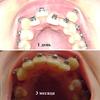

А вот когда мне кажется, что ничего не меняется, я смотрю на этот коллаж

Мне кажется, или правда челюсть расширилась за 3 месяца?